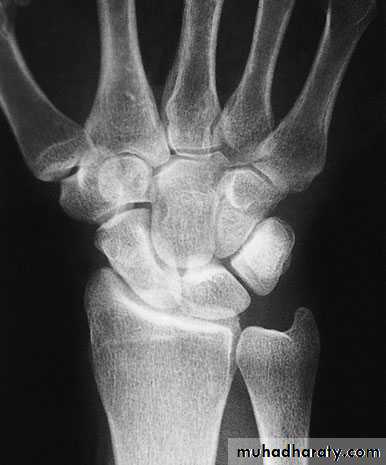

X-ray

Anteroposterior, lateral and oblique views are all essential; often a recent fracture shows only in the oblique view. Usually the fracture line is transverse,and through the narrowest part of the bone (waist), but it may be more proximally situated (proximal pole fracture). Sometimes only the tubercle of the scaphoid is fractured.Treatment